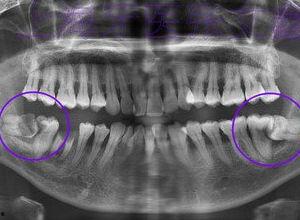

磨牙不仅会影响睡眠质量,还可能导致牙齿磨损、颞下颌关节疼痛等问题。而网络上的成人磨牙实录视频大全图片,正是这些磨牙者的真实写照。